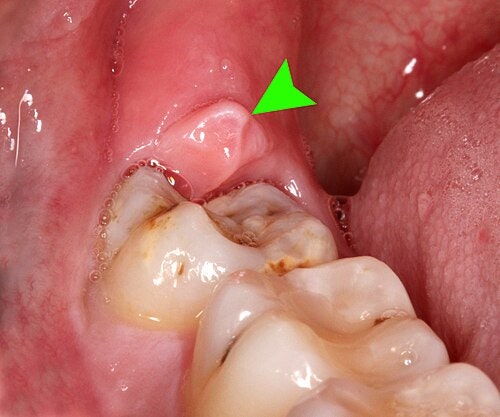

이렇게 심하게 부은 상태가 되면 이미 염증이 꽤나 진행된 상태라고 볼 수 있습니다. 치관주위염(Pericoronitis)가 생긴 경우로, 치료가 필요해요 (출처: https://en.wikipedia.org/wiki/Pericoronitis)

🦷 고름까지 보인다면, 무슨 상태일까요?

잇몸이 붓는 정도를 넘어서

👉 고름이 보인다면

이미 염증이 꽤 진행된 상태입니다 💥

이건

치관주위염(pericoronitis)이

급성으로 악화된 상태라고 볼 수 있어요.

사랑니 주변에 염증이 생긴 경우 통증, 안면통증, 잇몸에 고름, 잇몸 부어오름 등의 증상이 생깁니다 (출처: https://www.kwcdental.com/)